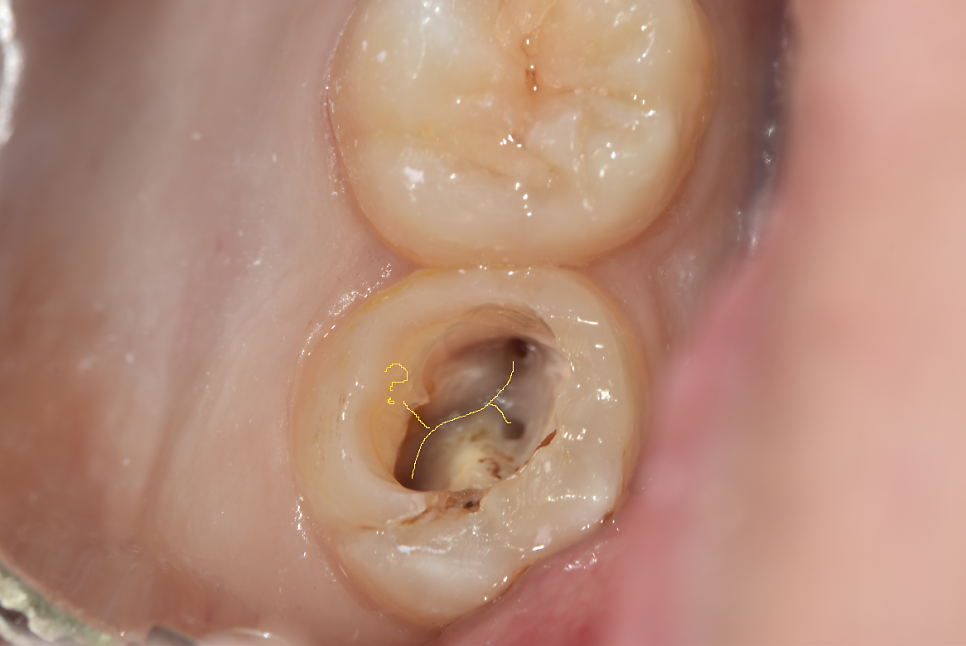

그리고 아래 두 장은 블로그에 올리지는 않았었지만, 저번 주에 기존 크라운 벗겨낸(그래서 프렙이 돼있다) 하악 제1대구치. 디스탈 근관 2개 다 찾았는데 드러난 DL치근 위치가 너무 돌출되어 있어서 해당 위치에 근관이 하나 더 있을 것으로 예상했었다. 그래서 이번 주 예약에 엔도Z버로 확장해 보니 실제로 근관 하나가 더 나왔다. 사실 이 치아는 처음엔 근관 찾으려고 찍은 사진이 아니고, 크라운 벗기고 AO 하니까 와동 바닥에 타DC에서 퍼포 시켜놓고 리페어를 했는지 도대체 알 수가 없는 치질 아닌 웬 이상한 게 있어서 찍어놓은 것이다. 근데 이게 뭘까~ 하고 사진을 가만 보다 보니 갑자기 디스탈에 근관 하나 더 있을 것 같아서 체크해놨었던 케이스.

EzDent에 그린 그림 (노란 선) 캡쳐

평소 진료하다가 이상한 게 있으면 DSLR로 찍어서 이렇게 EzDent(영상 프로그램)에 표시를 해놓는다. 혹시 다음번 내원하셨을 때 마침 내가 바빠서 대표원장님이 이 환자를 보게 되면 대표원장님께서 참고하실 수 있도록 찍기도 하고, 내가 다음번에 까먹을 수도 있고, 또 무엇보다 나 스스로 기록해 놓기도 좋고 해서 특이한 게 있으면 꼭 DSLR로 임상사진을 채득해 놓으려고 한다. 어디선가 구내 DSLR 촬영도 수가 산정을 해야 하는 거 아니냐고 하던데, 솔직히 나도 그 의견 지지한다💥 정말 필요한 일이야.